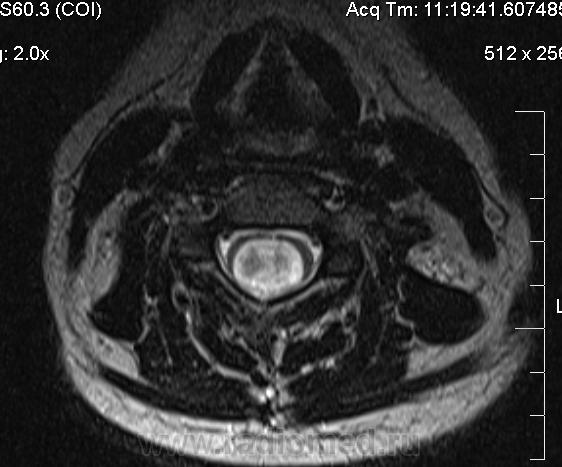

Сирингомиелия шейно-грудной локализации? Аномалия Арнольда-Киари I. Платибазия.

здоровенная сирингогидромиелитическая киста (по видимому, "высокого давления"), мальформация Киари 1.   также имеются признаки внутренней окклюзионной гидроцефалии.

А уровень окклюзии на уровне БЗО?

Думаю, да. У человека наверняка сильно болит голова.

Cпасибо большое, как вы думаете, это  кисты в области мягких тканей шеи справа (гиперинтеснивные по Т1 и Т2), или что-то другое?

морфологически- явно кистозные образования. А вот их происхождение - вопрос.